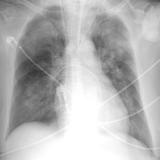

APE 4

Date: 11/05/2005

Views: 2825